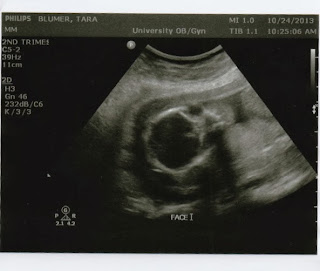

Friday, October 25, 2013

Gender Ultrasound

Yesterday we took Paige and Ashby out of class and we all hopped

into the car for a family outing the doctor's office. The kids were so

excited, of course, telling everyone they passed by that we were going

to find out if the baby was a boy or a girl.

Paige has been pretty vocal about hoping the baby was a girl. Brian felt strongly it was a girl. I figured it was about time for a girl. Levi said he wanted a little sister. Ashby was adamant it was another boy. And Cody just says Woohoo.

We thought viewing the ultrasound together would be a fun experience for everyone (though we knew it would be a lot of work for us - well, mostly Brian. I just had to lay there).

The room was

tiny, and it was very dark. The technician began her job looking around

at things, and measuring things, and finding all the organs....and it

was all pretty boring for the kids. We tried to make it exciting, but

they mostly just wanted to go back to the waiting room and finish the

movie.

The baby's legs were tightly closed so the technician did some jiggling and kept looking around. Eventually she found a pretty good shot and felt very confident in her analysis. When all the kids were paying attention she tried to describe and point (but who can ever really tell what's going on in those pics) and finally wrote BOY!!! on the screen.

Paige stood there silent. Ashby read the screen out loud to everyone and hooted and hollered. I probably just laughed (I've been laughing a lot the last day). When asked what she thought, Paige slunk to the floor against the wall.

When things had calmed down a bit Levi suddenly started crying and shouting hysterically, "I hate you Ashby!"

I was so confused, Ashby wasn't even standing next to Levi. "Why do you hate Ashby?"

"Because I wanted it to be a girl and he wanted a boy! Its all Ashby's fault!!"

Poor kid. He definitely took the news the hardest.

So, we get to have another boy at our house. I can't complain too much, they're pretty cute boys. Wednesday, October 16, 2013